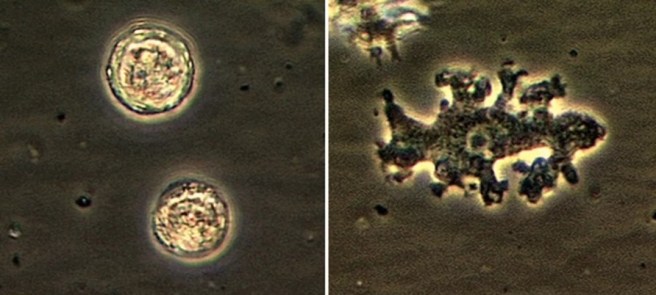

Médicos acreditam que o episódio, que culminou na morte da paciente, começou com a água que ela utilizou para limpar o nariz

Fonte: Caso raro de ameba que come cérebro termina em morte nos EUA